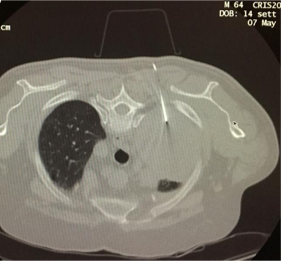

其中有10例患者,病灶直径>3cm ,PET扫描显示示踪剂吸收不均匀,在最大SUV值和最小SUV值各穿刺取样两次。 ![]() 平均直径6.3 说明病变较大 PET/CT 与CBCT 影像融合(技术1)

PET-CBCT的融合图像也可以考虑。CBCT可以通过现代血管造影系统获取CT横断面图像。结合专用的软件,使其成功地应用于指导经皮活检。 ![]() 通过工作站把先前患者的PET与CBCT的图像融合进行CBCT引导下的肺活检

通过CBCT经胸经皮肺活检是一种安全且有用的鉴别肺结节的方法。在大多数情况下,在怀疑肺癌的组织学诊断是必要的,以进行靶向治疗和寻找特定的突变。特别是,由融合图像18F-FDG-PET/CBCT提供的解剖和代谢信息提高了组织学诊断的准确性,降低了假阴性的数量和增加获得最终解剖病理诊断的概率。